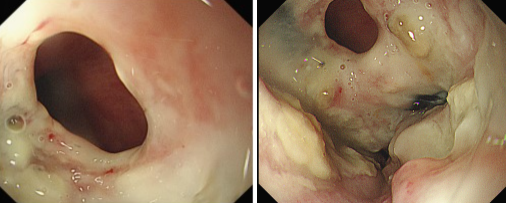

品質(zhì)國文 | 重獲進(jìn)食希望——內(nèi)鏡下食管覆膜支架植入手術(shù)

張大爺近期突然遭遇進(jìn)食困難,還頻繁出現(xiàn)進(jìn)食嗆咳的狀況。緊急檢查后,確診為食管惡性腫瘤,同時(shí)并發(fā)食管氣管瘺,而且因食物誤吸引發(fā)了肺部感染。由于瘺口的存在,食物不斷進(jìn)入氣道,致使嗆咳加劇、感染惡化,這不僅嚴(yán)重降低了張大爺?shù)纳钯|(zhì)量,更對(duì)其生命構(gòu)成了極大威脅。 閱讀量:1008